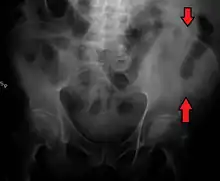

La cresta ilíaca es el nombre que recibe el borde superior del ala del ilion que se extiende hasta el margen de la pelvis mayor. La cresta ilíaca es palpable tanto en un hombre como en una mujer en toda su extensión,[1] de forma general convexa y levemente curva o sinuosa con concavidad interna en el frente y hacia afuera por detrás. Deja en su interior una cavidad que a menudo se denomina fosa iliaca.

La cresta ilíaca es más angosta hacia el centro que en los extremos y termina en la espina ilíaca antero-superior y posterior. La superficie de la cresta ilíaca es amplia y se puede dividir en un labio lateral o externo y un labio medial o interno y entre estos, una línea intermedia.[1]

La cresta ilíaca tiene una importante cantidad de médula ósea, incluso en el adulto, de modo que es un punto frecuente de extracción en la recolección de muestras de células madres para los trasplantes de médula ósea. El tope de la cresta ilíaca es el lugar donde se corresponde el cuerpo de la cuarta vértebra lumbar (L4), justo por encima o por debajo del cual se realiza la punción lumbar. La cresta iliaca es la mayor fuente de injerto óseo utilizada en cirugía maxilofacial, tanto de hueso esponjoso como de hueso corticoesponjoso.[3]